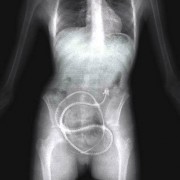

Можеби понекогаш се чувствувате виновно заради обилниот ручек што сте го изеле, но кога ќе видите што ставиле овие луѓе во својот стомак, ќе сфатите дека вие немате причина да се грижите. Барем не сте изеле батерии. Иако можеби имаат помалку калории, попрво би јаделе вкусни слатки со многу масти отколку киселински раствор. Луѓето имаат изедено некои многу чудни нешта…